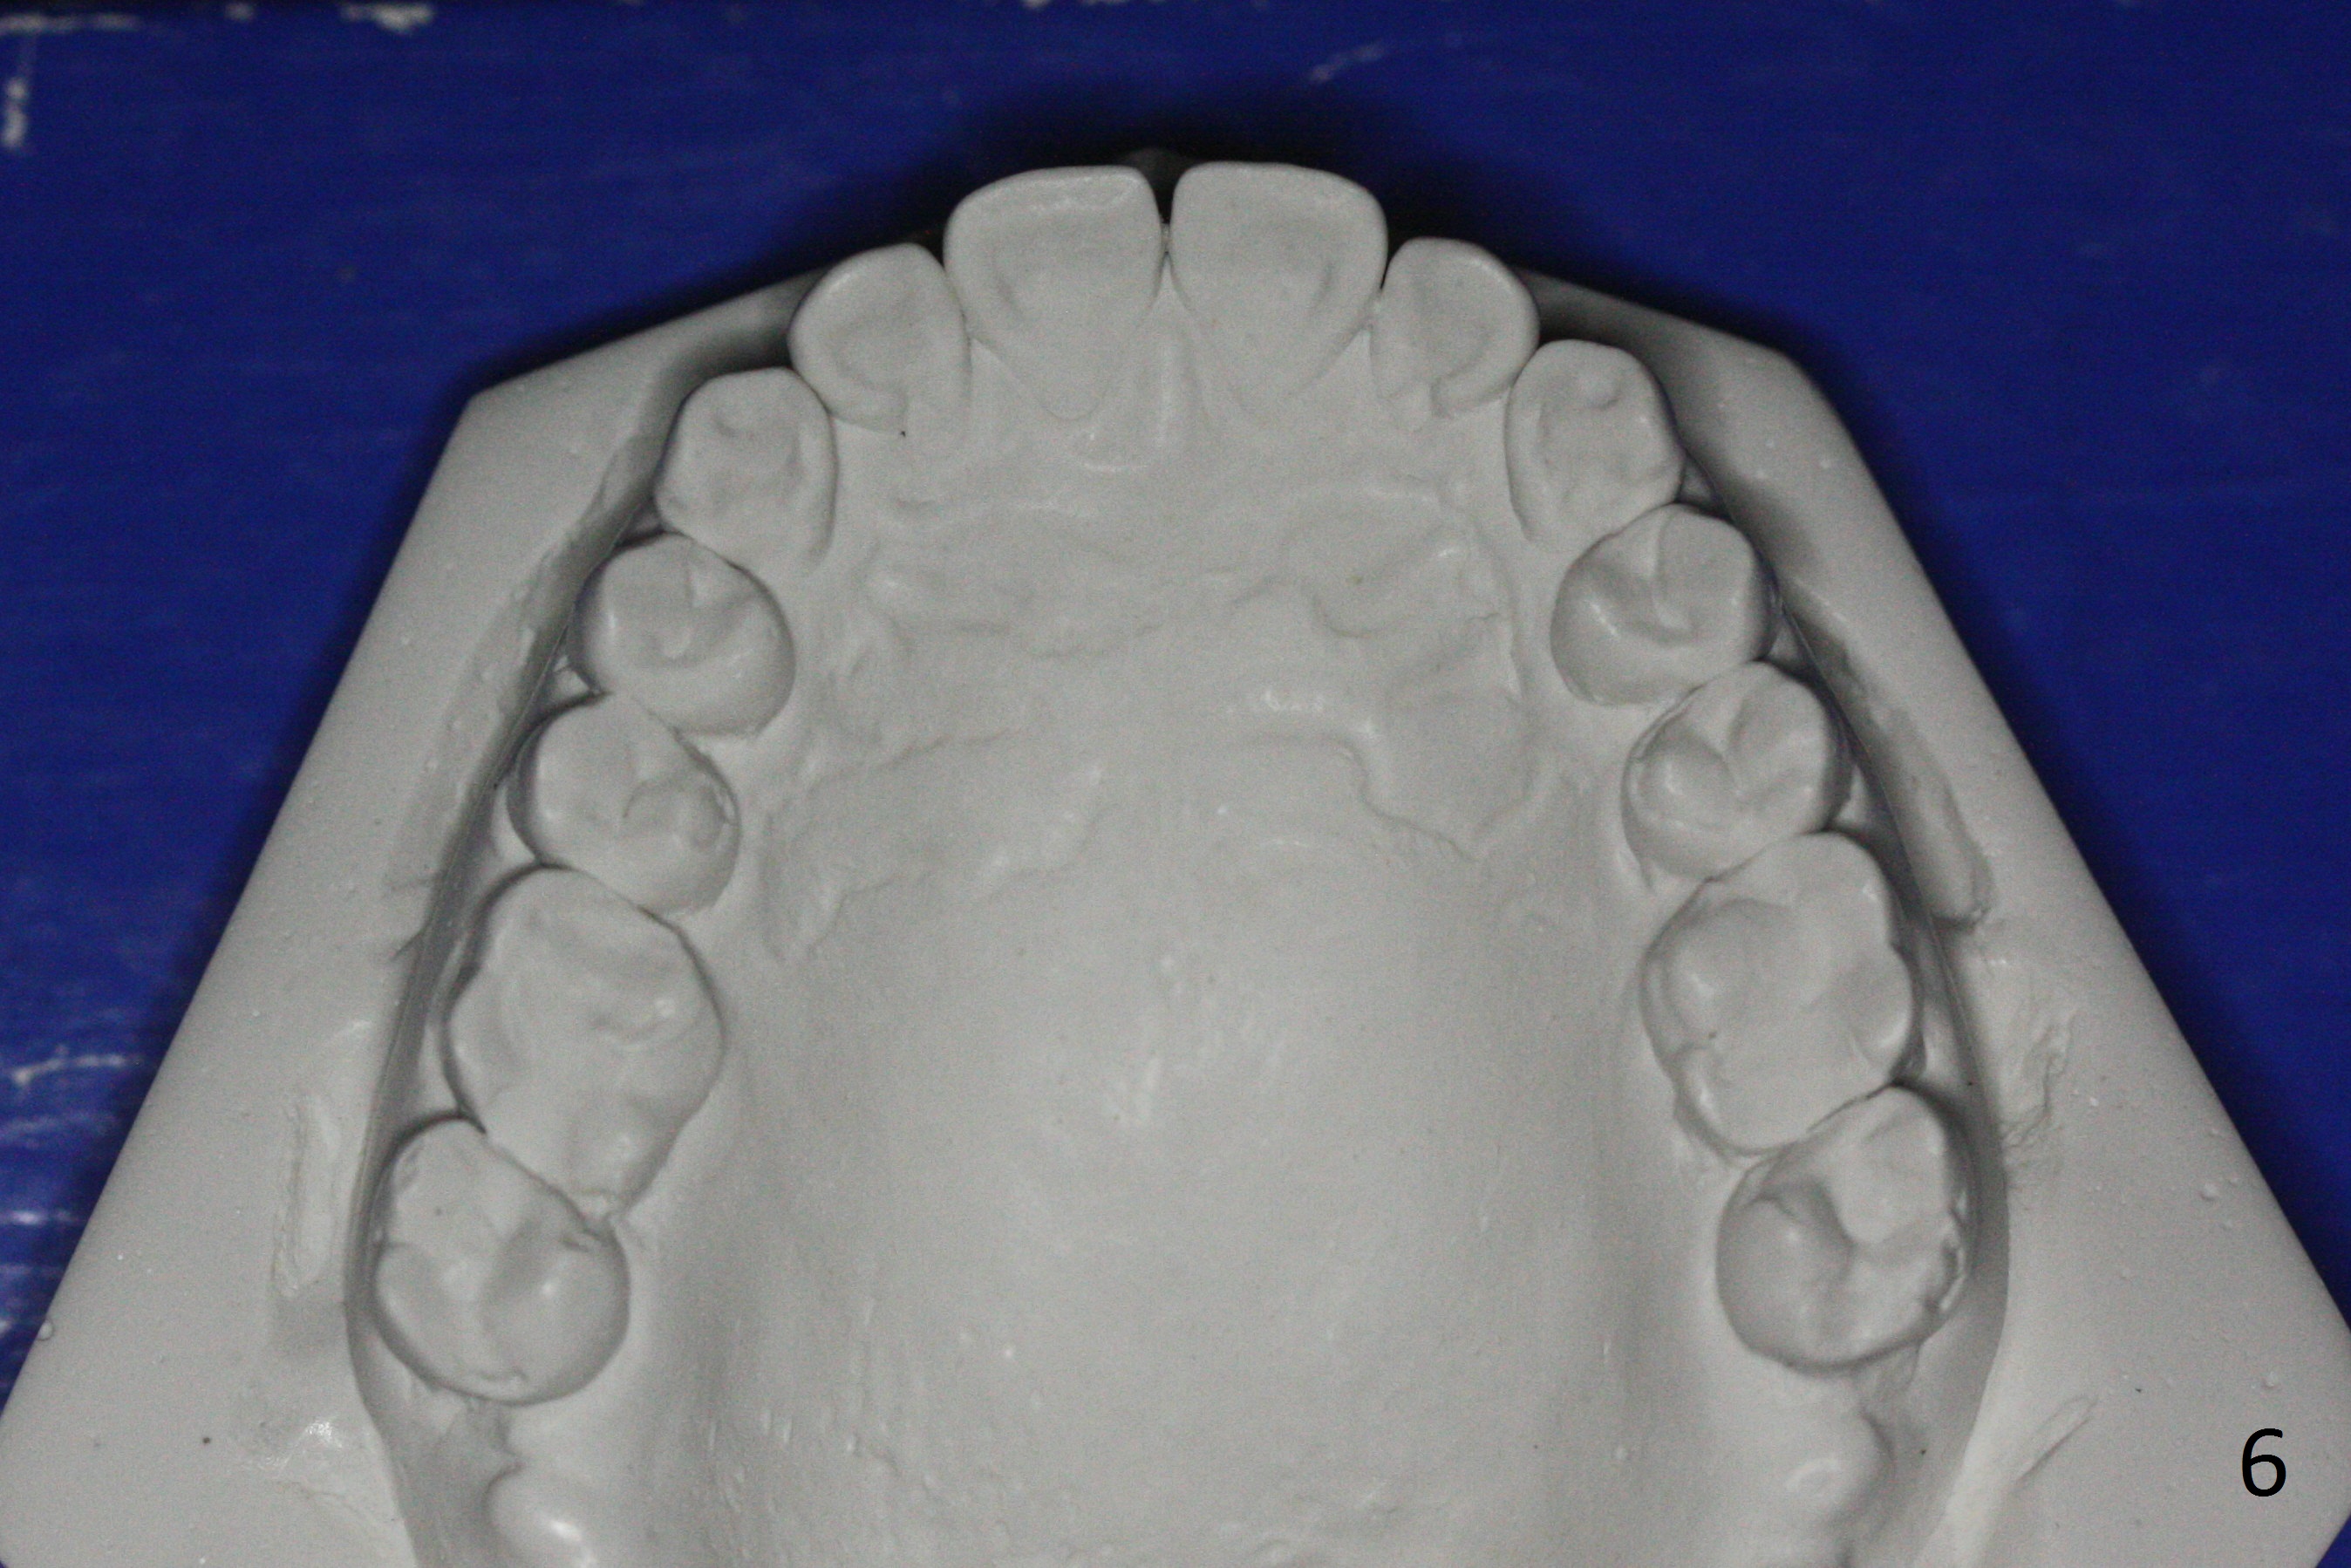

When orthodontic treatment is finished for a patient with crowding and anterior deep bite in 13 months, a diastema is found between the upper central incisors (Fig.2), which could be prevented by applying power chains for a few appointments prior to debanding. The upper anterior teeth look protrusive (Fig.4), proximal reduction seems necessary. Taking impression prior to debanding may reveal deficiency (Fig.5,6; 2nd good practice). The hidden diastemata can be revealed by use of 3-way syringe. The only prominent change is the reduction in the anterior deep bite (Fig.7,8 (posterior view)).

The 3rd good practice is to take 2 sets of Alginate impression so that there are 4 sets of postop models if impression is poured twice. Fabrication of suction down retainers may destroy the models. Retainers may be needed redo several years later. Some of patients prefer the 1st postop models. In short, extra models are beneficial. Extra care is required for the extra work, e.g., avoiding bubbles. The model will be saved in a secure way (good wrapping).